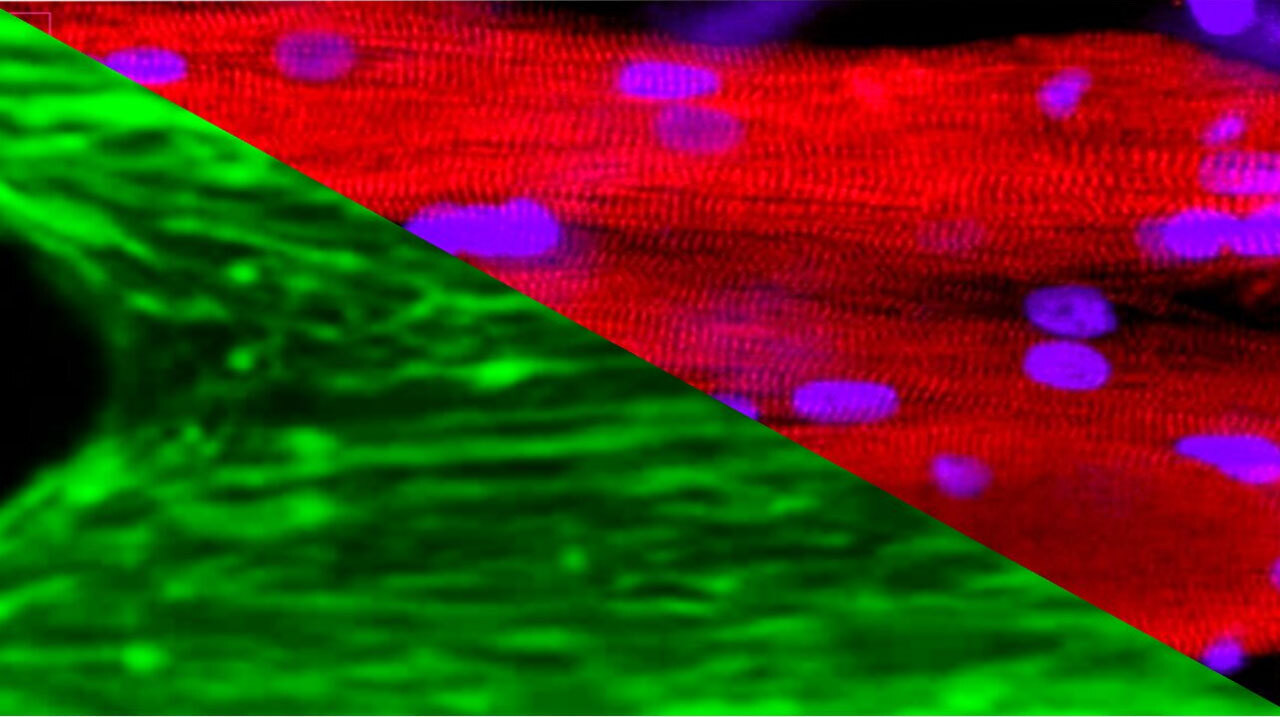

Исследователи из Флоридского университета взяли микроткани скелетных мышц из биопсий доноров и отправили их на Международную космическую станцию на борту SpaceX CRS-25 в формате «органы на чипе». Результаты эксперимента опубликованы в журнале Stem Cell Reports.

Микроткани были взяты как у молодых, активных доноров, так и у пожилых, малоподвижных людей, и культивировались в автоматизированной мини-лаборатории CubeLab, которая, помимо регулярного питания и мониторинга культур, также позволяла проводить электрическую стимуляцию для имитации физических упражнений.